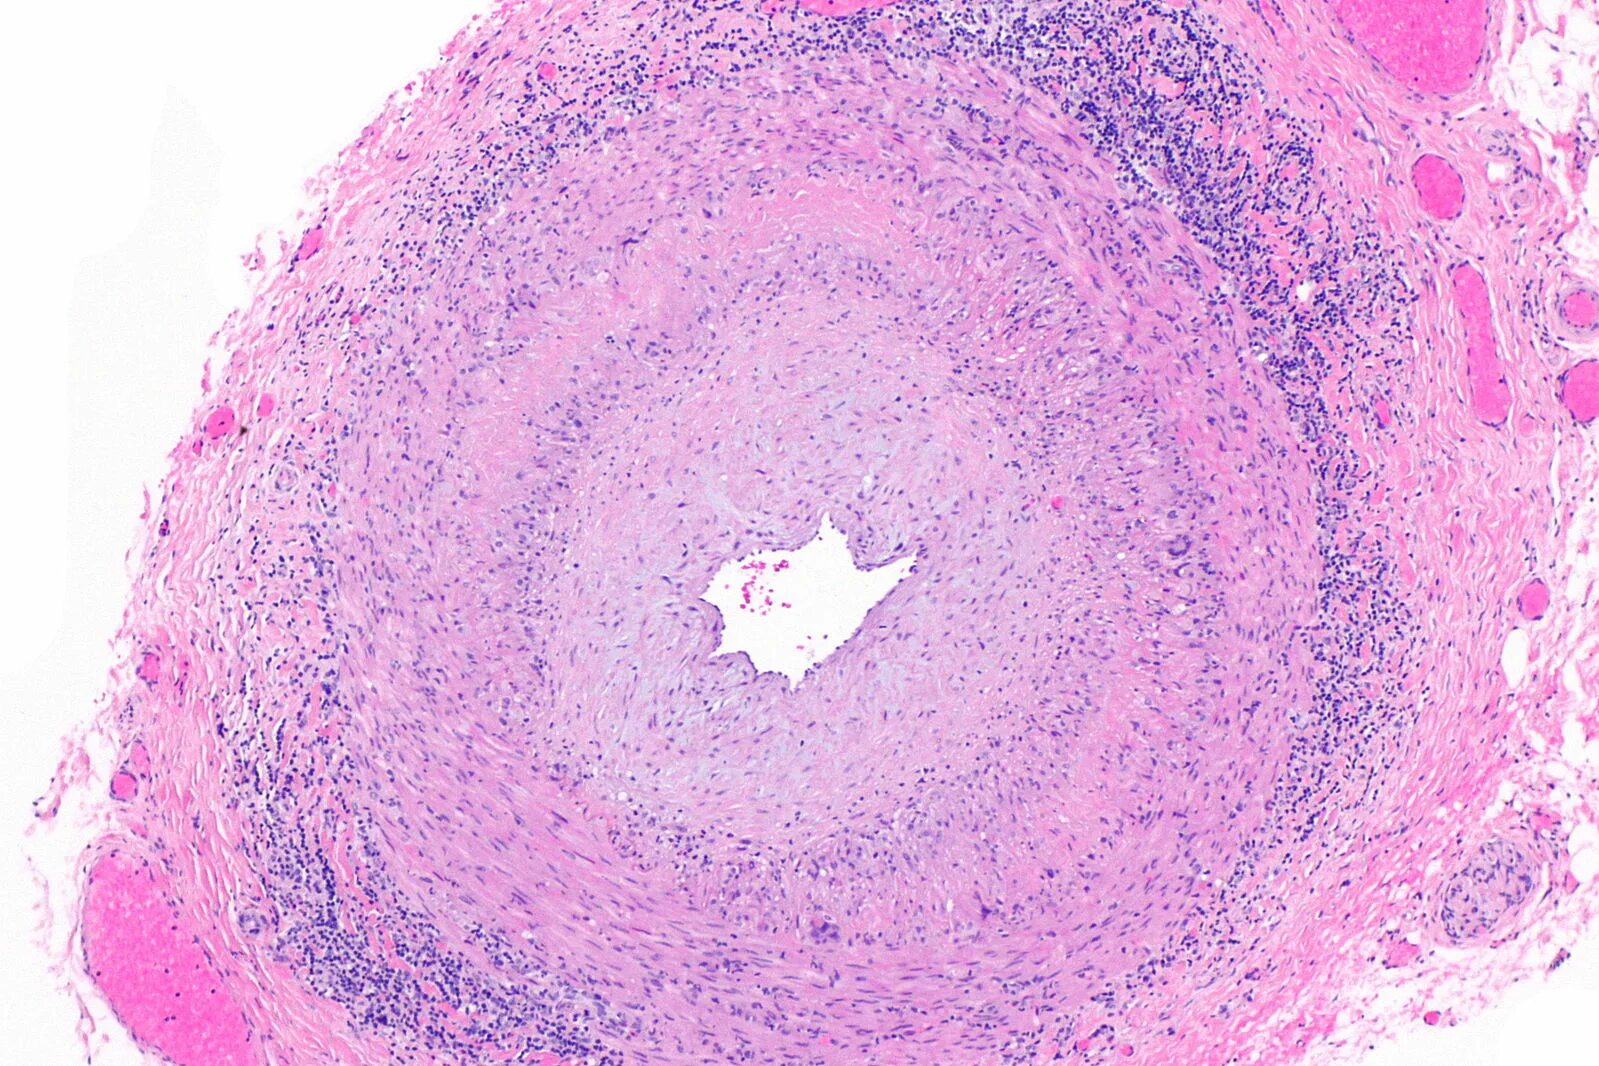

Гистология экология